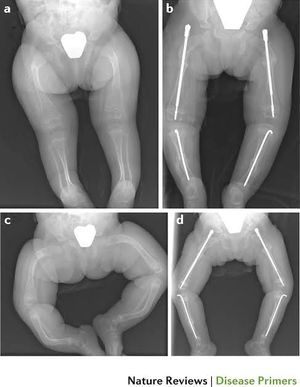

Osteogenesis imperfecta (OI) is a genetic disorder in which bones break easily. Sometimes the bones break for no known reason. OI can also cause weak muscles, brittle teeth, a curved spine, and hearing loss. OI is caused by one of several genes that aren't working properly. When these genes don't work, it affects how you make collagen, a protein that helps make bones strong. OI can range from mild to severe, and symptoms vary from person to person. A person may have just a few or as many as several hundred fractures in a lifetime. No single test can identify OI. Your doctor uses your medical and family history, physical exam, and imaging and lab tests to diagnose it. Your doctor may also test your collagen (from skin) or genes (from blood). There is no cure, but you can manage symptoms. Treatments include exercise, pain medicine, physical therapy, wheelchairs, braces, and surgery.